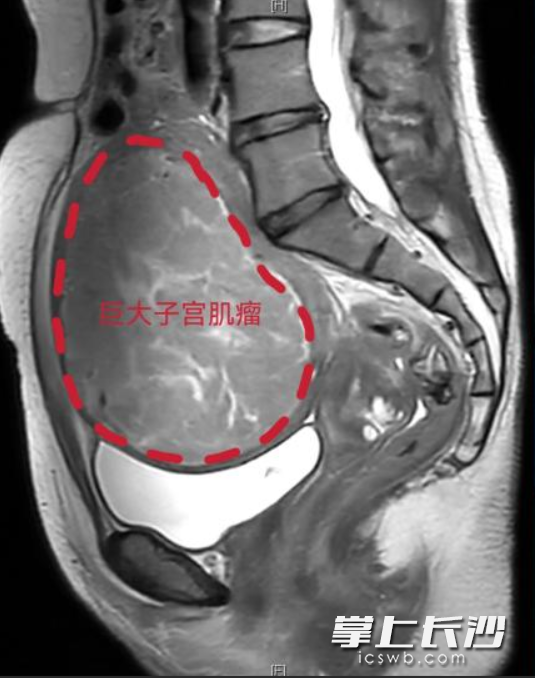

据陈女士介绍,近一年来,她每次来“例假”都像经历一场劫难:出血量特别大,时间也拖得长,人越来越没力气。在当地医院一查,肚子里竟悄悄长了个直径11厘米的巨大子宫肌瘤,像个小皮球,把子宫都压变形了。当地医院建议开腹手术切除子宫。一想到要切除子宫,肚子上面还要留下一条长长的疤痕,陈女士犹豫了。

巨大子宫肌瘤示意图。  医院供图